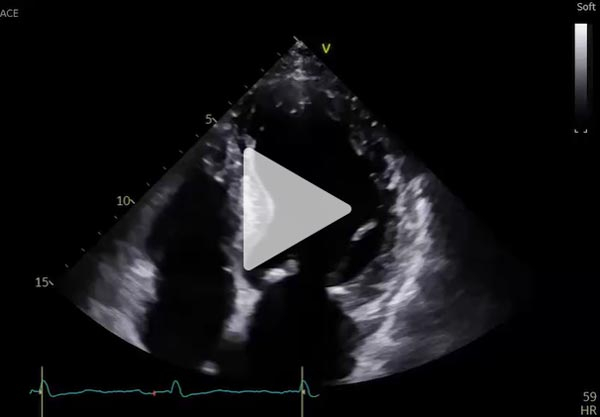

ETT de contrôle à 6 mois

- VG dilaté (DTDVG 58mm, VTDVG 78mL/m²) hypertrophié ( SIV 14mm ), FEVG modérément altérée, SBP 42%

- Petite IM centrale, pas de valvulopathie aortique

- PRVG normales, profil mitral en trouble de relaxation onde E 0.4m/s

- OG sévèrement dilatée

- VD non dilaté normokinétique

- PAPS estimées à 25mmHg, POD basse VCI fine compliante

- Péricarde sec

Vidéo 8 : incidence apicale 4 Cavités

Vidéo 9 : incidence apicale 4 Cavités